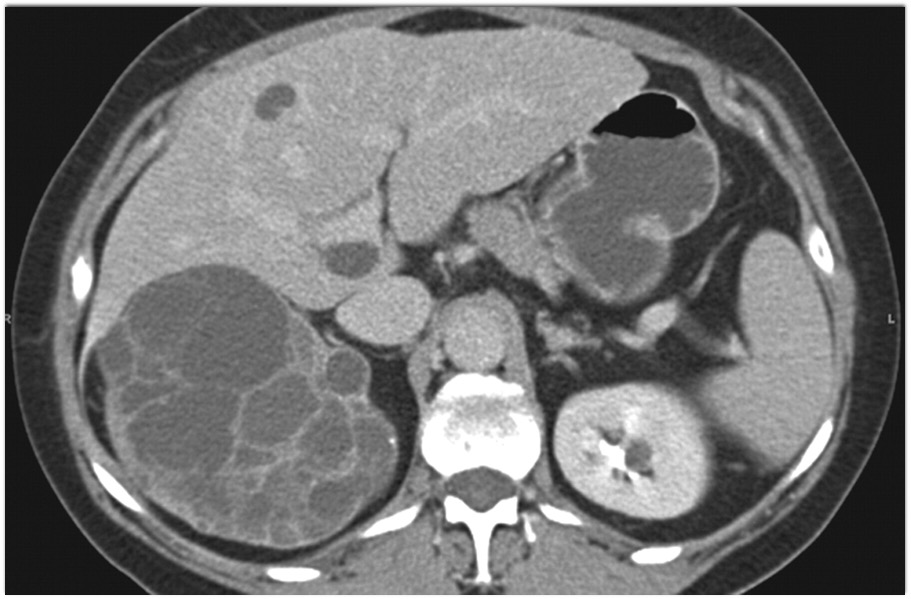

6) The most likely diagnosis in this 40ish year old female is

serous cystadenoma

mucinous cystic neoplasm (MCN)

IPMN

SPEN